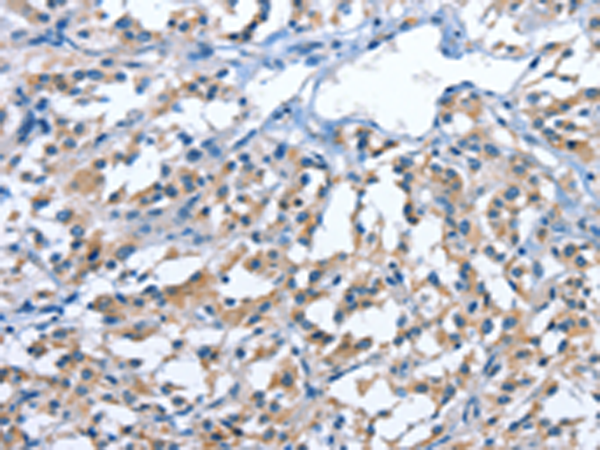

分类: 科研抗体货号: P07530别名: TFAR19应用: IHC反应种属: Human, Mouse